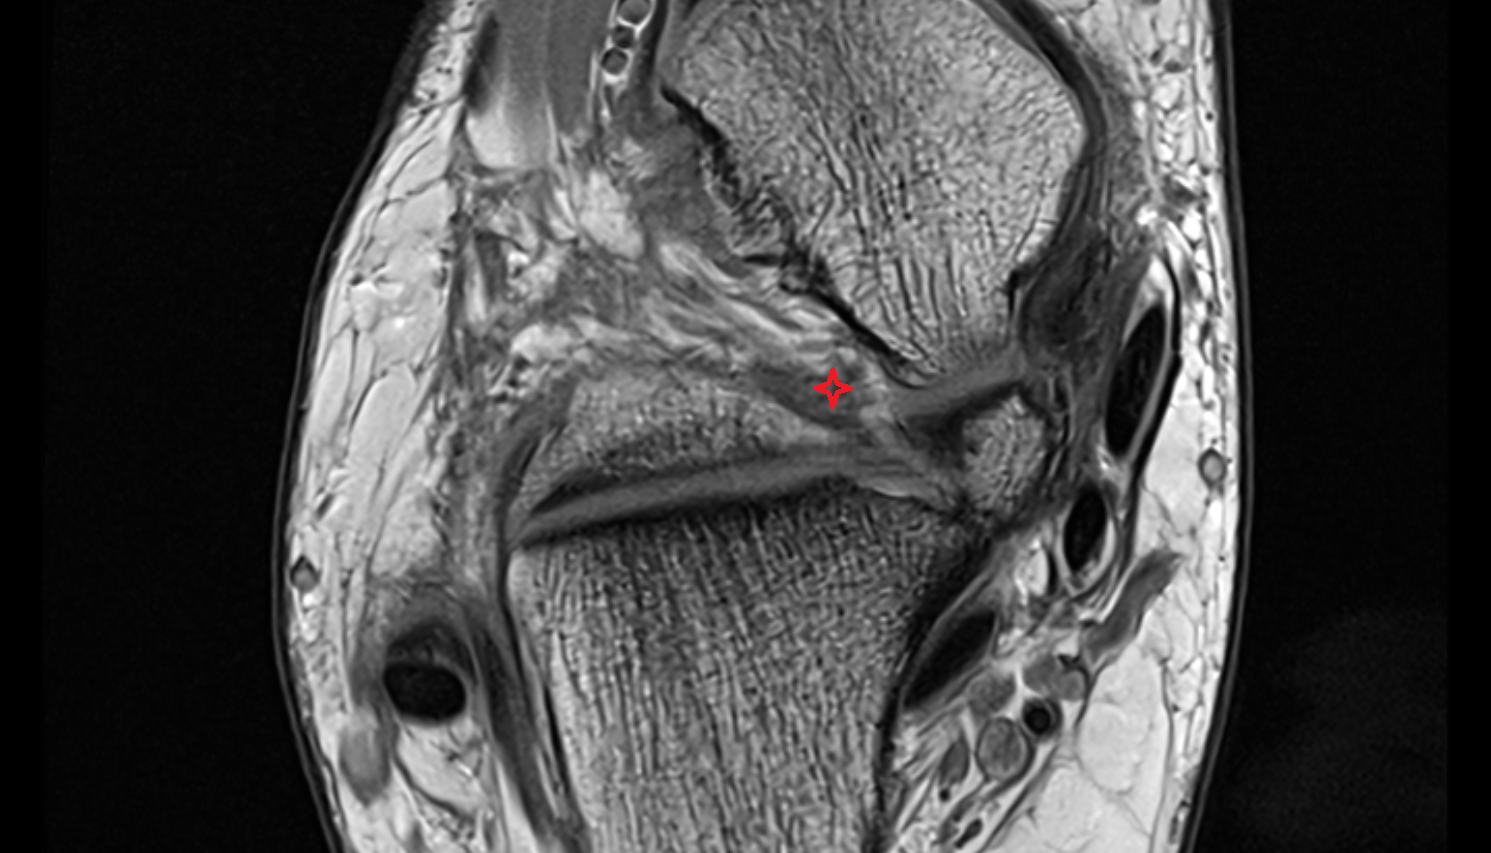

- Medial meniscus

- Lateral meniscus

- Anterior cruciate ligament

- Posterior cruciate ligament

- Medial collateral ligament

- Lateral collateral ligament